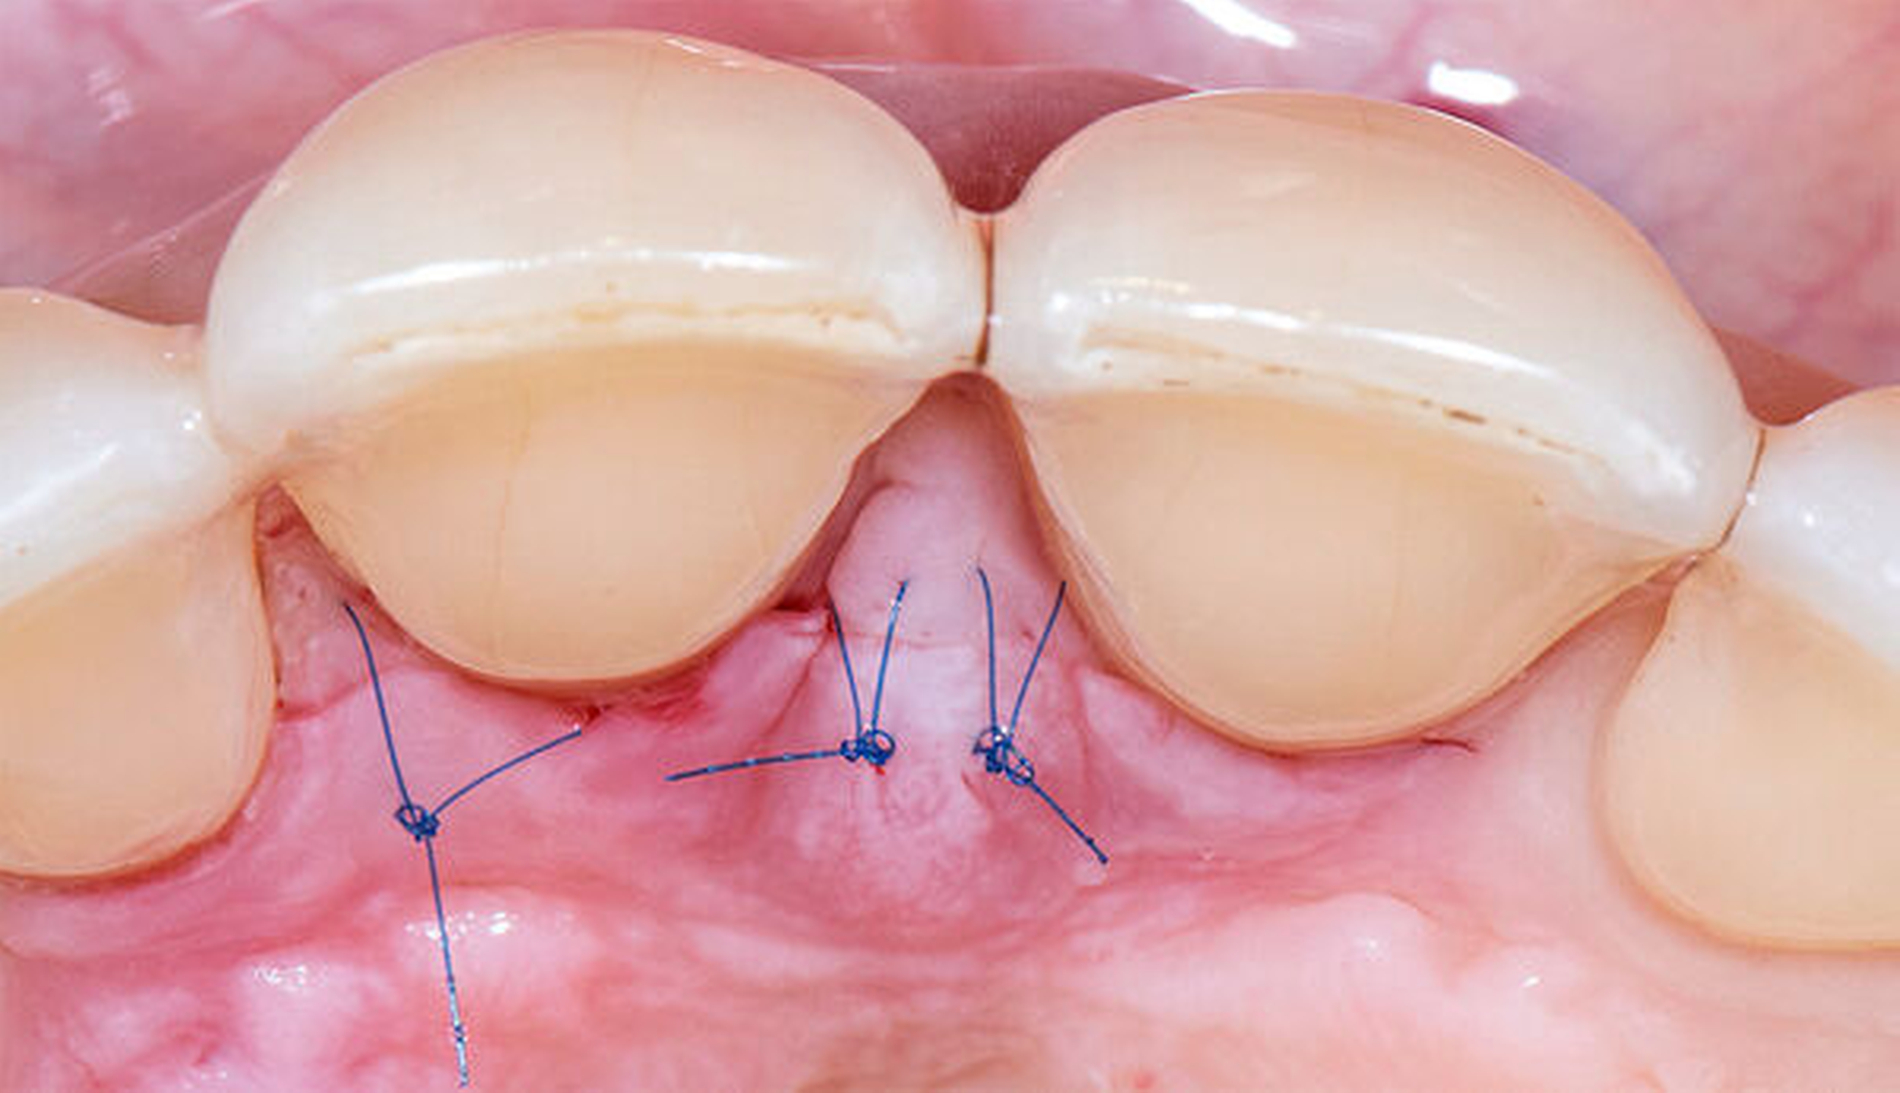

Bei einer Heilung per primam sind die Wundränder glatt, gut durchblutet, spannungsfrei aneinander liegend und präzise adaptiert. In der initialen, hämostatischen Phase bildet sich ein dünnes Blutgerinnsel zwischen den Wundrändern. Die Anhaftung dieses Koagulums fungiert als Abwehr gegenüber mechanischen Belastungen auf die präparierten Lappen [Wikesjö et al., 1991]. Blutplättchen geben Wachstumsfaktoren ab, die die Heilung einleiten. Es bildet sich eine Matrix aus weißen Blutkörperchen, die die Wunde bedeckt. Es kommt zu einer leichten Entzündungsreaktion, in deren Folge meist keine Gewebeschädigung verursacht wird. Die Gefahr einer bakteriellen Infiltration wird durch den Verschluss im oberflächlichen Bereich der Wunde nahezu vollständig vermieden [Cortellini & Tonetti, 2009]. Die Bildung von Narben- oder Granulationsgewebe wird minimiert, eine vollständige Ausheilung der Wundregion und eine Wiederherstellung der Gewebe ermöglicht (Abbildung 1).

In einer systematischen Literaturübersicht von Kang et al. wurde die Effek-tivität eines mikrochirurgischen Ansatzes bei der Behandlung gingivaler Rezessionen mit der Anwendung konventioneller makrochirurgischer Techniken unter Einbeziehung von vier randomisierten klinischen Studien verglichen [Kang et al., 2015]. Die mikrochirurgische Vorgehensweise erwies sich als vorteilhaft. Die Gründe scheinen in den exakt geplanten Inzisionen, atraumatisch präparierten Lappen und präzisen, spannungsfreien Wundverschlüssen zu liegen, die in der Mehrheit der Fälle eine primäre Wundheilung ermöglichten [Shanelec, 2003].

Während der Anfänge mikrochirurgischen Arbeitens in der Oralchirurgie zu Beginn der 1990er-Jahre wurden kurzerhand Instrumente und Nahtmaterialien aus anderen Fachdisziplinen, die die Mikrochirurgie bereits implementiert hatten, in die mikrochirurgische Parodontalchirurgie übernommen. Allein schon die Größe dieser Instrumente und Nadel-Faden-Kombinationen machte die Verwendung eines dentalen Operationsmikroskops während dieser Zeit obligat. Da sich jedoch die ergonomischen Anforderungen beispielsweise in der Gefäß- und Handchirurgie ganz wesentlich von denen oralchirurgischer Eingriffe unterscheiden, wurden nach und nach mikrochirurgische Instrumente und Nahtmaterialien speziell für den Einsatz in der oralen Mikrochirurgie entwickelt. Die doch sehr indi-viduellen und speziellen Anforderungen führten unter ergonomischen Gesichtspunkten zu vergleichsweise größeren und schwereren Instrumenten sowie dickeren und längeren Nadeln in Kombination mit dünnen Fäden der Größen 7.0, 8.0 und 9.0, wie sie bis heute in keiner anderen mikrochirurgischen Disziplin zur Anwendung kommen (Abbildungen 3 und 4). Als vorteilhaft erweist es sich vor diesem Hintergrund, dass die Dimensionen dieser gegenwärtig verwendeten Instrumente und Nahtmaterialien – Stand heute – problemlos mit Lupensystemen und Vergrößerungsfaktoren von 4.5x bis 6.0x eingesetzt werden können. Damit findet sich die orale Mikrochirurgie zum gegenwärtigen Zeitpunkt irgendwo zwischen konventioneller Makrochirurgie und traditioneller Mikrochirurgie mit dem großen Vorteil wieder, dass die Anwendung von Operationsmikroskopen mit den zuvor genannten Schwierigkeiten und Nachteilen nicht zwingend erforderlich ist.